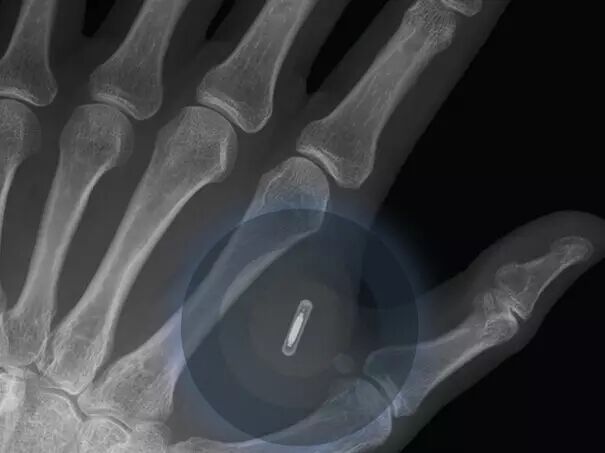

在2025年,首部可植入人体内的移动电话将问世

人类将可以在2023年将智能手机植入人体内。大约80%的被调查者预言在未来的7年内,人体内植入智能手机将可以用于商业。

而这种技术也能更准确地监控人们的身体健康情况,使人类在通过脑电波沟通方面又前进了一步。

植入式健康监控设备,比如计步器和人工耳蜗已经成为这类技术的主流,但是更多的植入式技术会在2025年之前与人们见面。